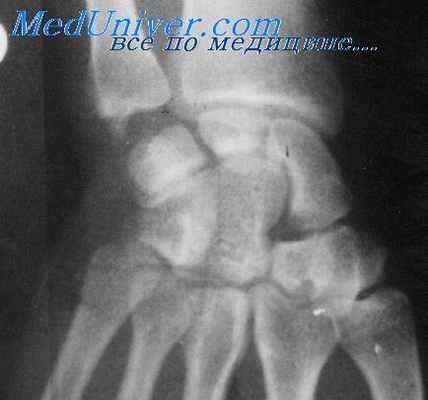

Лучезапястный сустав образован 8 небольшими костями, расположенными в 2 ряда, а также многочисленными связками, обеспечивающими сгибание и разгибание кисти, ее вращение вокруг продольной оси. Такая сложная конструкция существенно затрудняет диагностику и лечение патологий опосредованными методами – МРТ, рентгенографией, наружным осмотром и т.д. Поэтому «золотым стандартом» является артроскопия лучезапястного сустава – малоинвазивная хирургическая операция, позволяющая наблюдать проблемную область изнутри.

Рентгенография лучезапястного сустава проводится в двух проекциях. На самом снимке должны быть одновременно видны нижние трети костей предплечья, кости запястья, область лучезапястного сустава, отделы пястных костей, т.к. часто повреждение лучезапястного сустава путают с повреждением запястья.